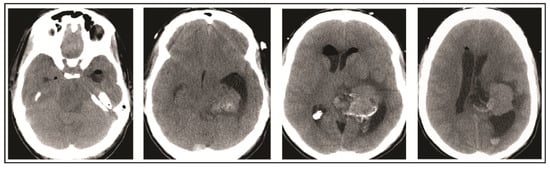

2. Case Presentation